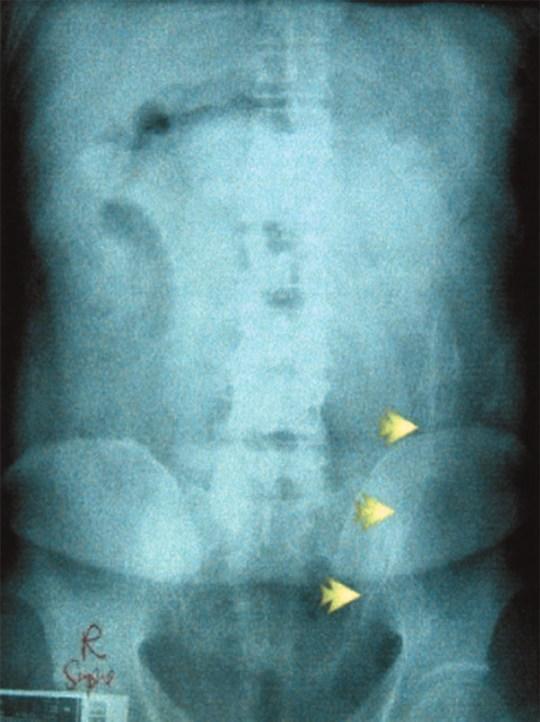

上个月,巴西某监狱一位男性囚犯肛门中被发现有8部带电的手机,4根USB线,7个手机芯片还有1根充电器电线…

他当时是刚到达监狱,接受电子检查,体内的电子装置直接被扫描仪显示出来了。

好家伙,这琳琅满目的电子产品,感觉在监狱里开个手机店都不成问题了。

他这也是靠“非法偷渡”挣钱,把这些手机、充电线都包好了塞进屁股,通过人体运送进监狱,分给需要的狱友,交易完成之后他就能得到一笔相应的钱。